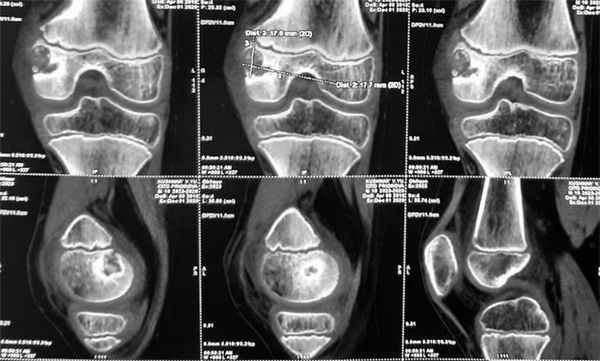

(Слева) Рисунок: срез проксимального отдела плечевой кости с типичной хондросбластомой. Показан эпифизарный, эксцентрично расположенный очаг с четкими границами. Патологическое образование имеет склеротический край и содержит кальцинаты.

(Справа) Рентгенография: классическая хондробластома у пациента с почти зрелым скелетом. Литический очаг развивается в эпифизе и распространяется на метафиз. Очаг не содержит кальцинированный матрикс, имеет четкие границы и умеренно склерозированный край. (Слева) МРТ, корональная проекция, режим Т1: однородный, эксцентрично расположенный эпифизарный очаг, типичный для хондробластомы. В зоне метафиза визуализируется массивная периостальная реакция типичный признак в 50% случаев.

(Справа) КТ, аксиальная проекция, без контрастного усиления: весьма эксцентрично расположенная хондробластома эпифиза плечевой кости. Она содержит небольшое вкрапление кальцинированного матрикса и немного вспучивает кортикальный слой. Этому пациенту с жалобами на боль и пощелкивание при ротации плеча, в первую очередь, вместо лучевого исследования, было необоснованно выполнено артроскопическое вмешательство.